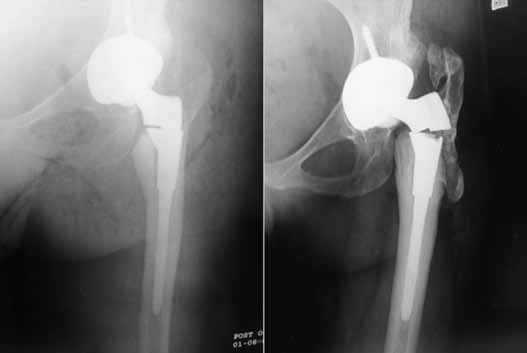

Изображение положения эндопротеза в теле человека.

Дислокация бедренного компонента на рентгене.